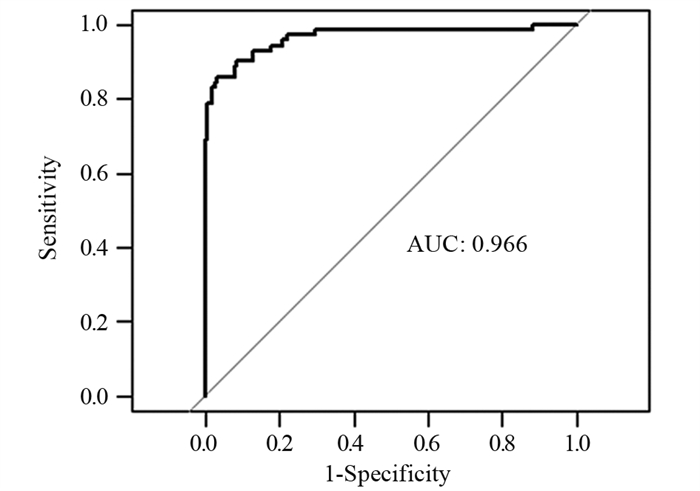

结果年龄、BMI、低分化、Lauren分型为弥漫型是胃癌术前N分期不足的独立危险因素(P < 0.05)。术前N分期不足组预后生存显著差于准确组(P=0.041)。预测模型的ROC曲线AUC为0.935,敏感度为85.9%,特异性为96.9%。

MethodsA retrospective method was used to analyze the clinicopathological data of 268 patients with gastric cancer. The patients routinely underwent preoperative thin-section enhanced CT to assess preoperative N-stage. Results The risk factors for preoperative N-stage deficiency were analyzed in combination with postoperative pathological findings. Multifactorial logistic regression analysis was performed to determine influencing factors, and Kaplan-Meier analysis was used to plot the survival curves of preoperative N-stage accurate group and deficiency group. The nomogram plot and ROC curves of the prediction model were drawn using the R package. AUC, 95%CI, sensitivity, and specificity were calculated.

ResultsAge, BMI, poor differentiation, and Lauren's classification as diffuse were independent risk factors for preoperative N-stage deficiency in gastric cancer (P < 0.05). Prognostic survival was significantly worse in the preoperative N stage-inadequate group than that in the accurate group (P=0.041). The AUC area was 0.935, with a sensitivity of 85.9% and specificity of 96.9%.